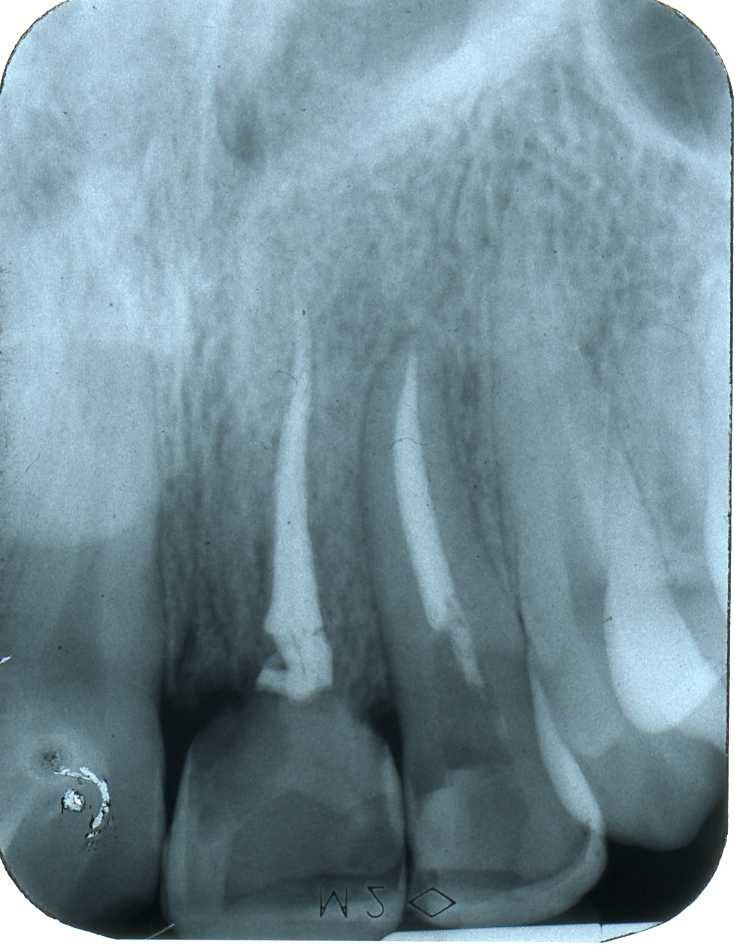

Radiograficamente è visibile il trattamento endodontico dell’incisivo laterale sinistro coinvolto anch’esso nel trauma. Sono visibili inoltre i dispositivi ortodontici necessari pe la sua estrusione al fine di recuperare l’ampiezza biologica, ovvero al fine di mantenere tre millimetri di tessuto dentale sano oltre il margine gengivale

Immagini radiografiche successive è possibile seguire negli anni l’evoluzione del dente reimpiantato. Nel corso degli la radice dell’incisivo centrale è andata in contro ad un progressivo riassorbimento per un atteso fenomeno di anchilosi.

L’anchilosi è un processo biologico infiammatorio che si verifica una volta che le fibre del legamento parodontale sono andate in necrosi e la superficie del cemento che ricompre la radice viene in contatto diretto con l’osso alveolare. In questa circostanza si attiva nei macrofagi una differenziazione in senso osteoclastico e dentino clastico che in pochi anni, talvolta in pochi mesi, porta al completo riassorbimento della radice e quindi alla sua scomparsa